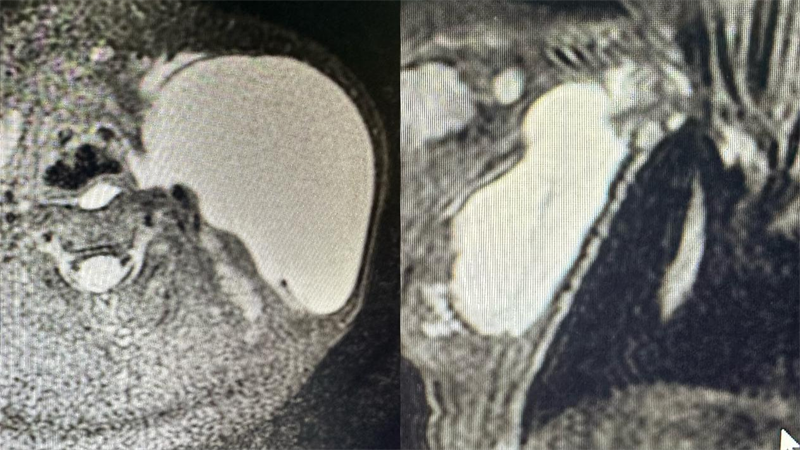

儿童淋巴管畸形磁共振检查

【辅助检查】1、超声检查提示无回声区,有分隔,呈囊状改变,CDFI:无血流信号,2、磁共振检查提示长T1长T2信号,囊状改变,压脂序列呈高信号,增强无明显强化。目的:1、超声检查用于明确诊断,2,磁共振检查用于了解淋巴管畸形病灶范围、侵及周围组织情况以及是否包绕重要器官如血管神经以及气管等。